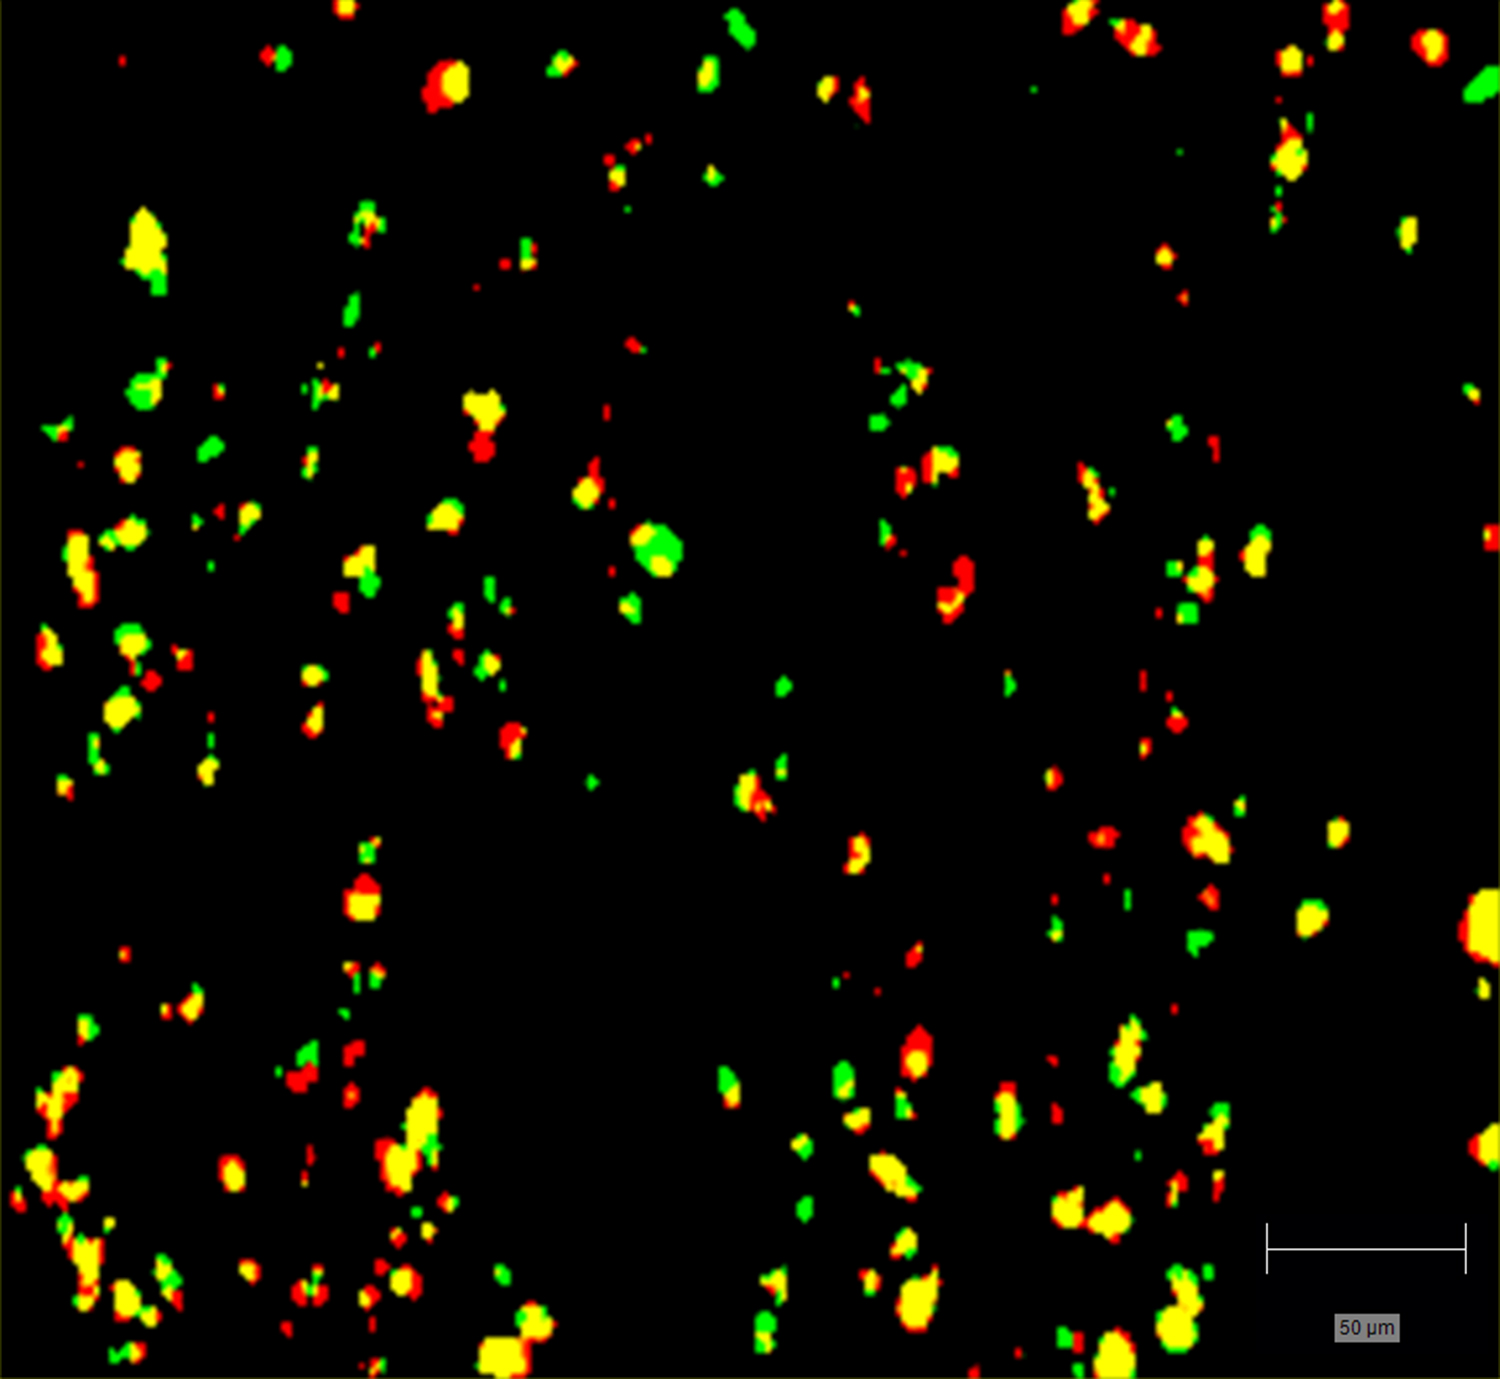

- Generate images of the formulations used in tablets, inhalers and nasal sprays at sub-micrometre spatial resolution

Rapidly generate images of your formulations with StreamLine™. This uses line focus illumination, allowing you to use higher laser powers without risk of sample damage, thereby reducing experiment times.

Generate images of formulations

Ensure your chemical images are representative; use Renishaw's StreamLine. You can change resolution to suit your domain size and, because Renishaw's WiRE software can cope with massive data files, you can analyse over the entire sample surface. Powerful Renishaw features, such as Slalom (to ensure the whole surface is sampled) and HD imaging (to get crisp clear images), provide all the options you need, whatever your formulation.